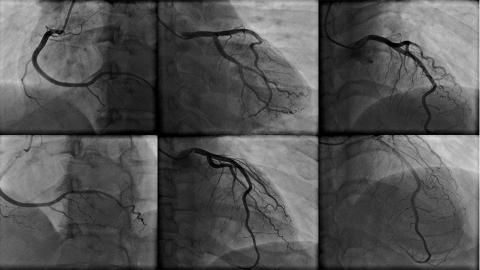

REACTU-Image n°47

Reactu